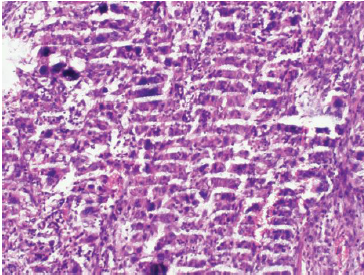

冰凍切片實驗是生物學(xué)、病理學(xué)、神經(jīng)科學(xué)等多個領(lǐng)域常用的實驗技術(shù),通過快速冷凍組織并進行切片,可以保留組織的原始結(jié)構(gòu)和抗原性,為后續(xù)的研究提供有價值的樣本。然而,冰凍切片實驗過程中常常會遇到一些問題,這些問題可能導(dǎo)致實驗結(jié)果的偏差,甚至影響整個實驗的成敗。冰凍切片實驗常見問題以及解決方法由普拉特澤生物為大家總結(jié)分享,普拉特澤生物動物實驗平臺專業(yè)承接HE染色實驗外包、Masson染色等病理染色實驗代做服務(wù),積累專業(yè)豐富的實驗操作經(jīng)驗。本文將對冰凍切片實驗中常見的問題進行分析,并提出相應(yīng)的解決策略。

七、切片染色效果不佳

切片染色效果不佳可能是由于染色時間過長或過短、染色液濃度不合適等原因造成的。